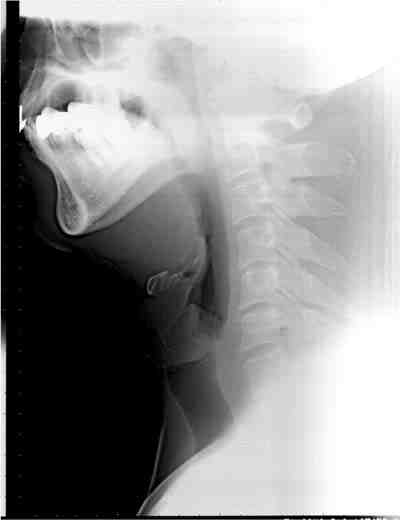

Sleep splint(口腔内装具)の効果

装具装着前

装具装着後

下顎が前方に移動し,気道が広くなっています。(黒い部分が空気の通り道です。)